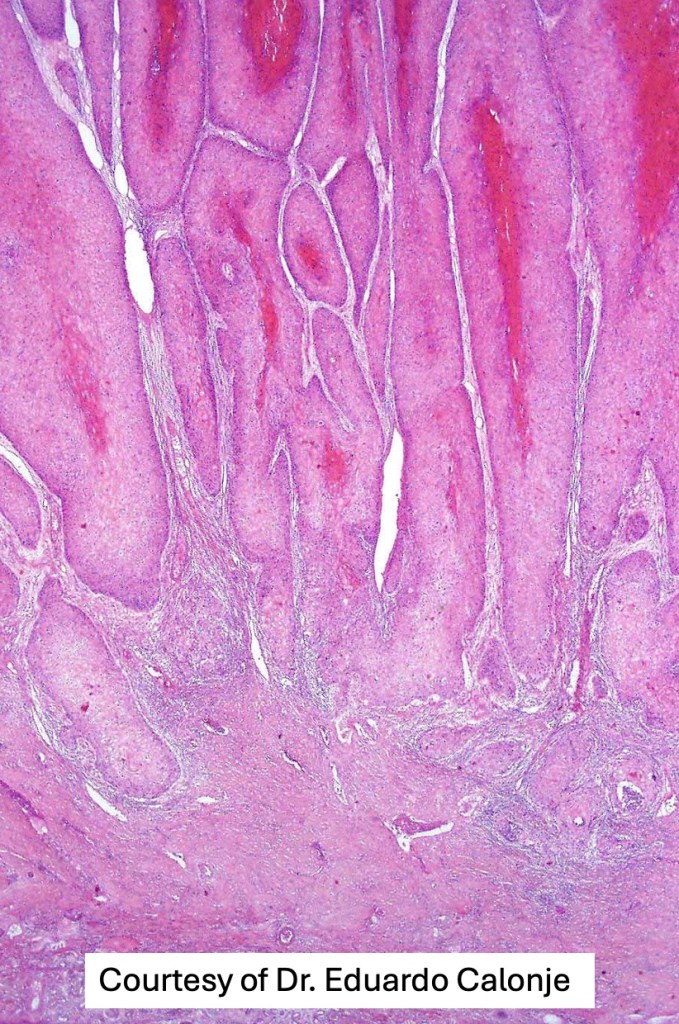

•Often massive hyperkeratosis

•Epidermal verrucous hyperplasia

•Deeply penetrating bulbous processes with a pushing rather than infiltrating lower border